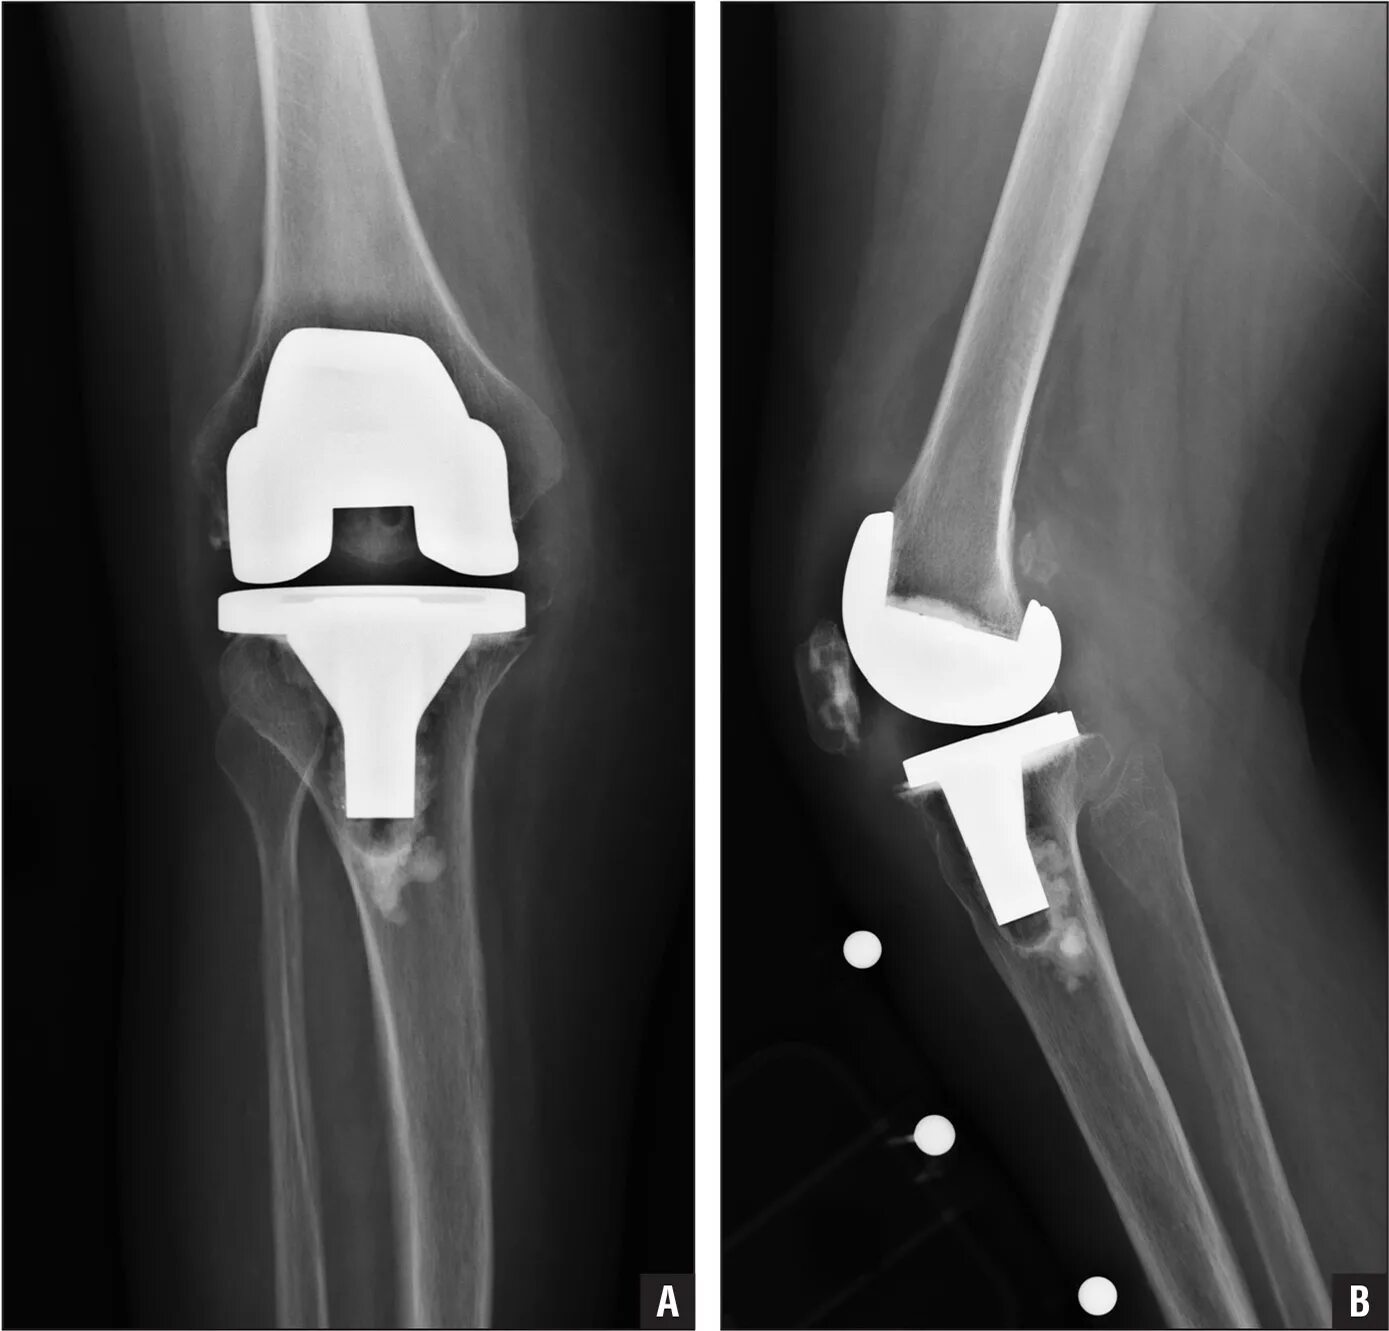

Эндопротез тазобедренного сустава москве